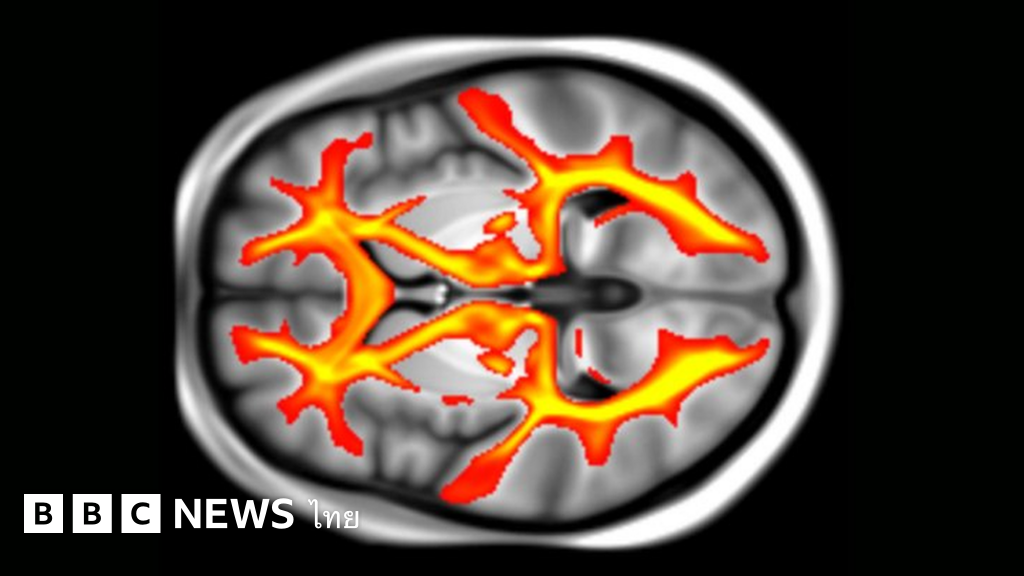

ที่มาของภาพ, UNIVERSITY OF OXFORD

รายงานวิจัยที่ตีพิมพ์ในวารสาร Nature Communications ระบุว่า มีการวิเคราะห์ผลสแกน MRI จากสมองของกลุ่มตัวอย่าง 22,000 ราย ที่มีอายุระหว่าง 40-70 ปี ซึ่งผลสแกนนี้ได้จากคลังข้อมูลชีวภาพ UK Biobank

จากนั้นทีมผู้วิจัยได้พิจารณาผลสแกนสมอง โดยดูว่ามีความเปลี่ยนแปลงของ pathway หรือวิถีการเชื่อมต่อของเนื้อสีขาว (white matter)ในสมองส่วนต่าง ๆ อย่างไรบ้าง ทั้งเปรียบเทียบความเปลี่ยนแปลงเชิงโครงสร้างนี้กับข้อมูลสุขภาพ และความสามารถในการคิดของกลุ่มตัวอย่างแต่ละคนด้วย

ผลปรากฏว่ากลุ่มตัวอย่างที่มีปัจจัยเสี่ยงต่อโรคหลอดเลือดสมองสูง ซึ่งส่วนใหญ่ก็คือผู้ที่มีความดันโลหิตสูง เกิดการเปลี่ยนแปลงของวิถีเชื่อมต่อระหว่างเนื้อสมองสีขาวไปอย่างมาก แม้จะยังอยู่ในวัยเพียงสี่สิบกว่าปีเท่านั้น โดยดร. มิเชล เวลด์สแมน ผู้นำทีมวิจัยจากมหาวิทยาลัยอ็อกซ์ฟอร์ดของสหราชอาณาจักรบอกว่า